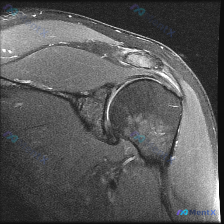

整理了一份肩部MRI病例讨论材料,医生的核心问题是排查盂唇病变,但看影像发现了一些矛盾点。先放MRI T2序列冠状位的分析: 1. 骨性结构:肱骨头、肩峰及锁骨远端轮廓尚可,未见骨折线或骨髓水肿 2. 肌腱与肩袖:冈上肌腱在肱骨大结节止点处形态异常,连续性中断,T2高信号 3. 关节与滑囊:肩峰下-...

最近看到一个肩关节病例,资料里主要有一张肩关节冠状位T2加权MRI。患者可能有肩部症状,假设是盂唇病变,但影像上的表现有点矛盾。先放影像分析的核心点: 1. 盂唇结构:关节盂上、下边缘的盂唇信号正常,边缘锐利,未见高信号裂隙或旁囊肿,没看到典型的盂唇撕裂征象。 2. 肩袖肌腱:冈上肌肌腱附着于肱骨大...